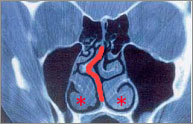

鼻中隔とは鼻の真ん中のしきりのことです。軟骨の板と、骨の板とでできています。顔の発育とともに鼻も発育しますが、骨より軟骨の板のほうが発育が盛んなので、その違い(ひずみ)のために彎曲(わんきょく)がおこります。誰でも多少鼻は曲がっていますが、いつも鼻がつまって口呼吸やいびき、においがわからないなどの症状がある場合は手術で直します。これを鼻中隔矯正術といいます。 下の患者さんは、右に凸の鼻中隔彎曲症です(オレンジ太線)。また、特に左側に肥厚性鼻炎を認めます。

鼻腔の側壁から出ているヒダのようなものを下鼻甲介(上記写真の「」部分)といいます。粘膜が厚かったり、骨がとび出ていたりすると肥厚性鼻炎になります。症状は、とにかく鼻が一日中詰まりっぱなしで、点鼻薬(血管収縮剤)もだんだんと効果がなくなってきます。これを直すのが、粘膜下下甲介骨切除術(とびでている骨を削る)、下鼻甲介粘膜切除術(厚くなった粘膜を削る)です。